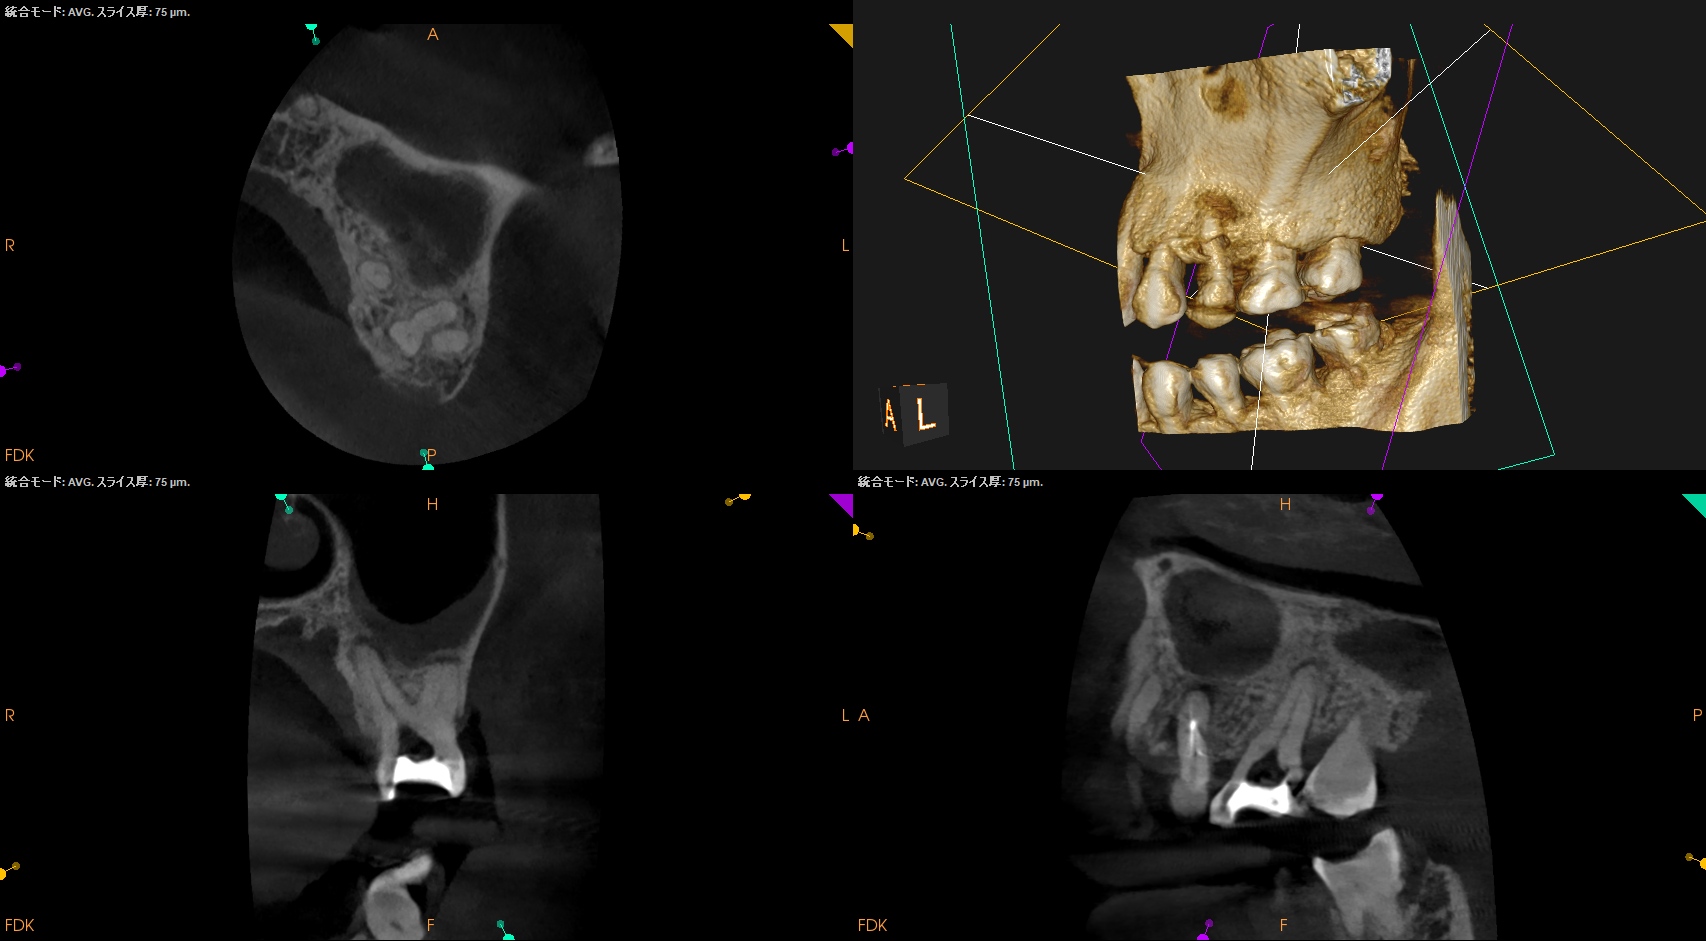

おおよその作業長が類推できる。

が、いずれにしてもこの治療での最大のポイントになるのはMB2がどこにあるか?である。

MB2の根尖部にはCBCTで根尖病変があるからだ。

作業長が術前に予測したCBCTでの作業長に近似していること

を。

これが、

CBCTの威力

である。

ということで、術後にPA, CBCTを撮影した。

#14

MB1

MB2

DB

P

#14 Pは外部へBC sealerが溢出したが、

文献的には押し出されたそれは、

で、問題はないと考える。

当歯科医院のケースでもそれが最終的には臨床上は消失しているように見えて症状も消失していることが確認されているので問題視してない。

#13